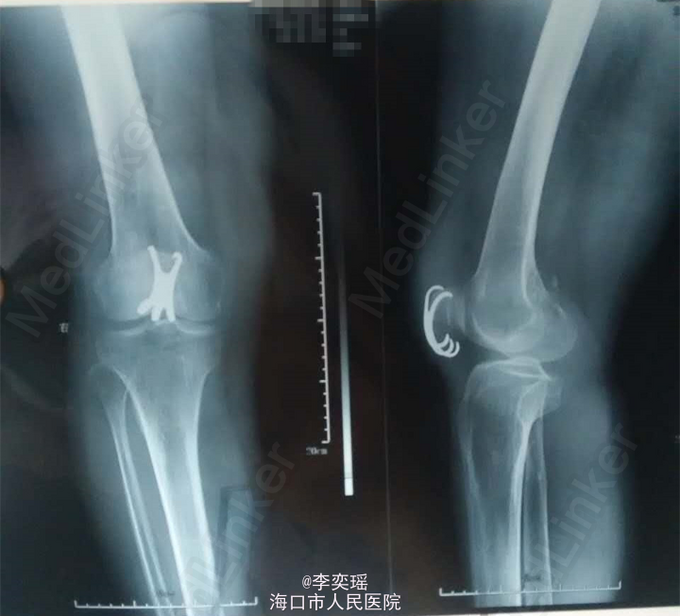

专科体查:右膝部中度肿胀,局部皮肤青紫,无皮肤破损。压痛,可扪及明显骨擦感及闻及明显骨擦音。右膝关节活动受限,浮髌试验(+),肢端感觉,血运好,趾活动好。左下肢,双上肢,脊柱活动好,无畸形。 辅助检查:右膝关节正侧位:右髌骨骨折

入院诊断:右髌骨骨折